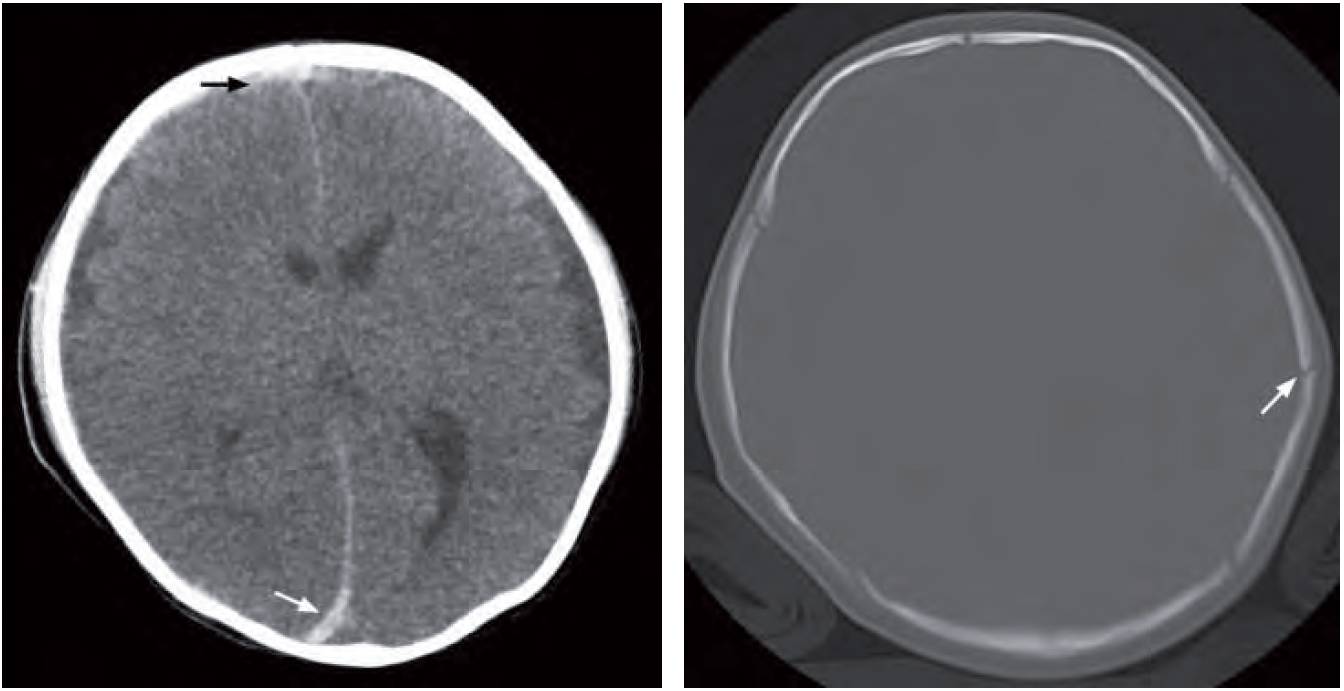

- Acute right frontal subdural and interhemispheric haematoma – due to shearing force from shaking the baby resulting in rupture of small vessels crossing subdural spaces

- Non-depressed fracture of left parietal bone with no associated intracranial or scalp haematoma

Right image: Bone window of CT brain shows a non-depressed fracture in the left parietal bone (arrow). This is an old fracture as there is no associated intracranial or scalp haematoma.

Non-accidental injury (from shaking the baby) resulting in acute right frontal subdural haemorrhage and interhemispheric subdural haemorrhage along the posterior aspect of falx.